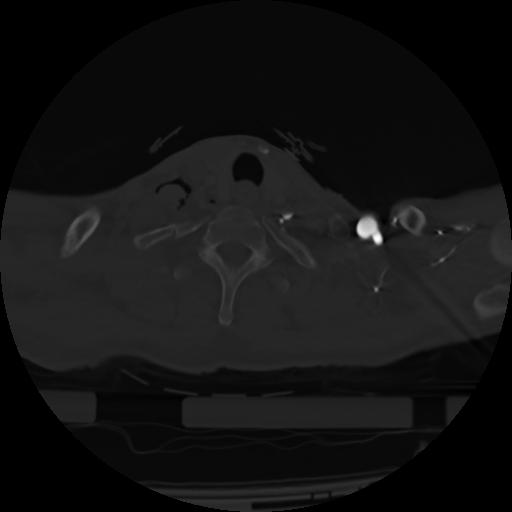

21 ANGIO,CE,Axial,3.0,ANGIO,,